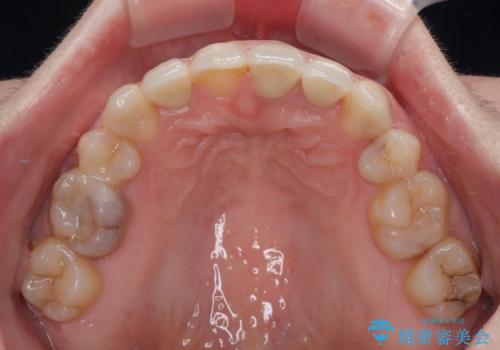

- 前歯のデコボコと、その結果むし歯が進行していることを気にして来院された患者様です。

前歯や奥歯の根管治療を行い、その後上下左右の第一小臼歯4本を抜歯してワイヤー装置にて矯正治療を行うこととしました。

矯正治療後には、根管治療を行った歯をオールセラミッククラウンにて補綴治療を行うこととしました。

治療途中で激務の会社に就職することとなり、なかなか矯正治療に通院することができなくなり、治療期間が想定の2倍近くとなりましたが、無事に満足のいく形で治療を終えることができました。